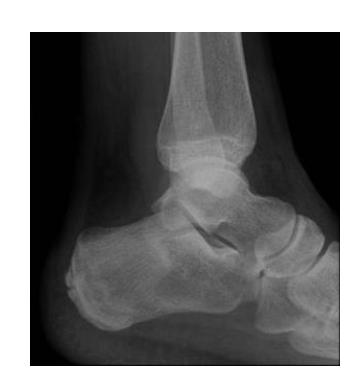

Ankle Specific Fractures

General Ankle Fracture

Diagnosis: Ankle fracture Mechanism: Twisting injury Common in: Old people

Mortise View of the Ankle